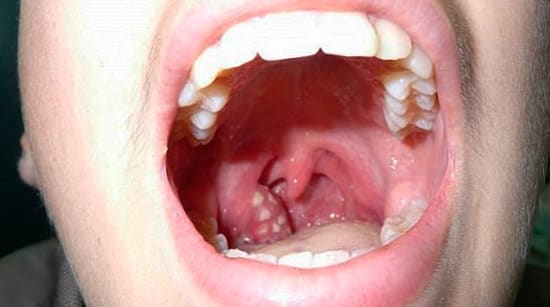

На изображении видно белый гной на миндалинах, лечение которого следует начинать незамедлительно после его обнаружения, так как длительное накопление может привести к перекрытию дыхательных путей, что действительно угрожает жизни.

Пробки выглядят как беловатые твердые образования, расположенные в лакунах. В редких случаях, когда в миндалинах образуется жидкий гной, лечение не требуется, так как такое состояние может пройти самостоятельно, хотя воспалительный процесс продолжается. Если заболевание повторяется систематически, гнойники могут увеличиваться, и болезнь прогрессирует. В таком случае следует немедленно обратиться к специалисту.